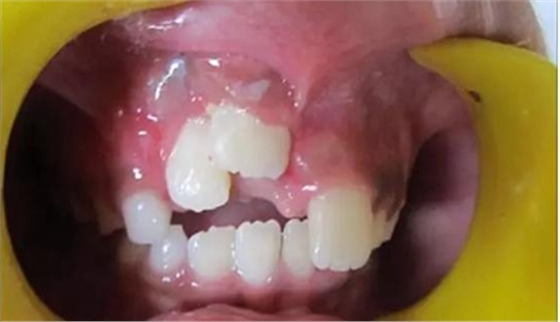

健康的 7 歲男童,前一天摔倒,上頜右中切牙和右側(cè)切牙發(fā)生挫入脫位(圖 1)。無(wú)牙外傷史,無(wú)神經(jīng)并發(fā)癥病史。檢查發(fā)現(xiàn)雙側(cè)下頜下腺增大。

口腔內(nèi)發(fā)現(xiàn):混合牙列早期,覆蓋正常,安氏I類磨牙關(guān)系。牙11和12齦緣紅腫。

牙11,12 和21對(duì)叩診敏感。牙11嚴(yán)重挫入(牙11和牙12的切緣相差7毫米),并挫入牙槽窩。與牙21相比,牙12大約挫入4毫米。

診斷:牙11嚴(yán)重挫入,牙12中度挫入,牙21震蕩傷。